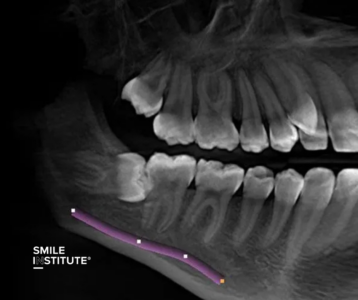

Amikor egy páciens fogászati problémával érkezik, az első és legfontosabb lépés a pontos diagnózis felállítása. A hagyományos panorámaröntgen ugyan sok esetben megfelelő információt nyújt, de vannak helyzetek, amikor ez nem elegendő. A fogászati CT (CBCT – Cone Beam Computed Tomography) lehetővé teszi, hogy a fogorvos háromdimenziós képet kapjon a teljes állcsont szerkezetéről, beleértve a rejtett problémákat is, amelyeket egy hagyományos röntgen nem tud kimutatni.

A fogászati diagnosztikában többféle röntgenfelvételt alkalmaznak, attól függően, hogy milyen információkra van szükség. A panorámaröntgen az egyik leggyakrabban használt típus, amely az egész fogsort és az állkapcsot mutatja. Ez különösen hasznos bölcsességfogak vizsgálatánál, fogszabályozás tervezésénél vagy implantáció előtt.

A kis fogászati röntgen (intraorális felvétel) részletesebb képet ad egy-egy fogról, így kiválóan alkalmas a szuvasodások vagy gyökérkezelési problémák feltárására. A fogászati CT (CBCT) pedig háromdimenziós képet biztosít az állcsont és a fogak szerkezetéről, így komplexebb beavatkozások előtt – például implantátum vagy szájsebészeti műtétek esetén – elengedhetetlen.

➜ Foghúzás és bölcsességfog eltávolítás esetén: A komplikált fogeltávolítások során a CT segít meghatározni az idegek és az érintett fogak pontos helyzetét, elkerülve a szövődményeket.

» Bölcsességfogak elhelyezkedésének feltérképezése